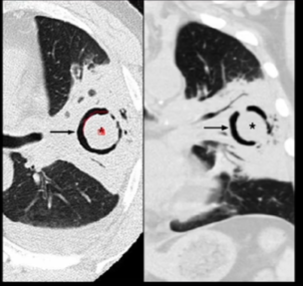

14

Q

Sinais e padrões torácicos

Qual o sinal apresentado da imagem?

A

Sinal do Halo Invertido

Consolidações periféricas cirundando opacidades em vidro fosco

15

Sinal do Crescente Aéreo

Definição

*Coleçaõ de ar em formato de crescente (C) que seprada um nódulo/ massa da parede de uma cavitação.

*Costuma ser um achado benigno